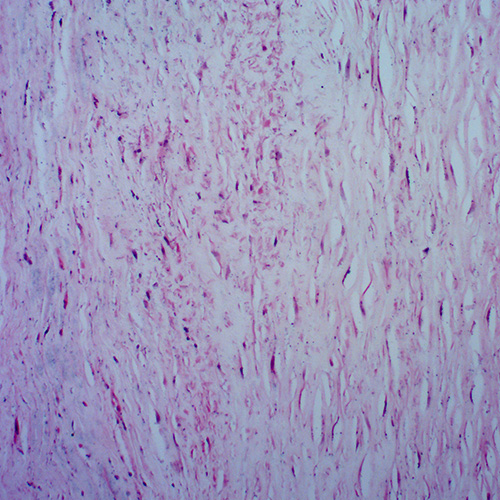

辽宁人体心血管及呼吸系统疾病玻璃玻片